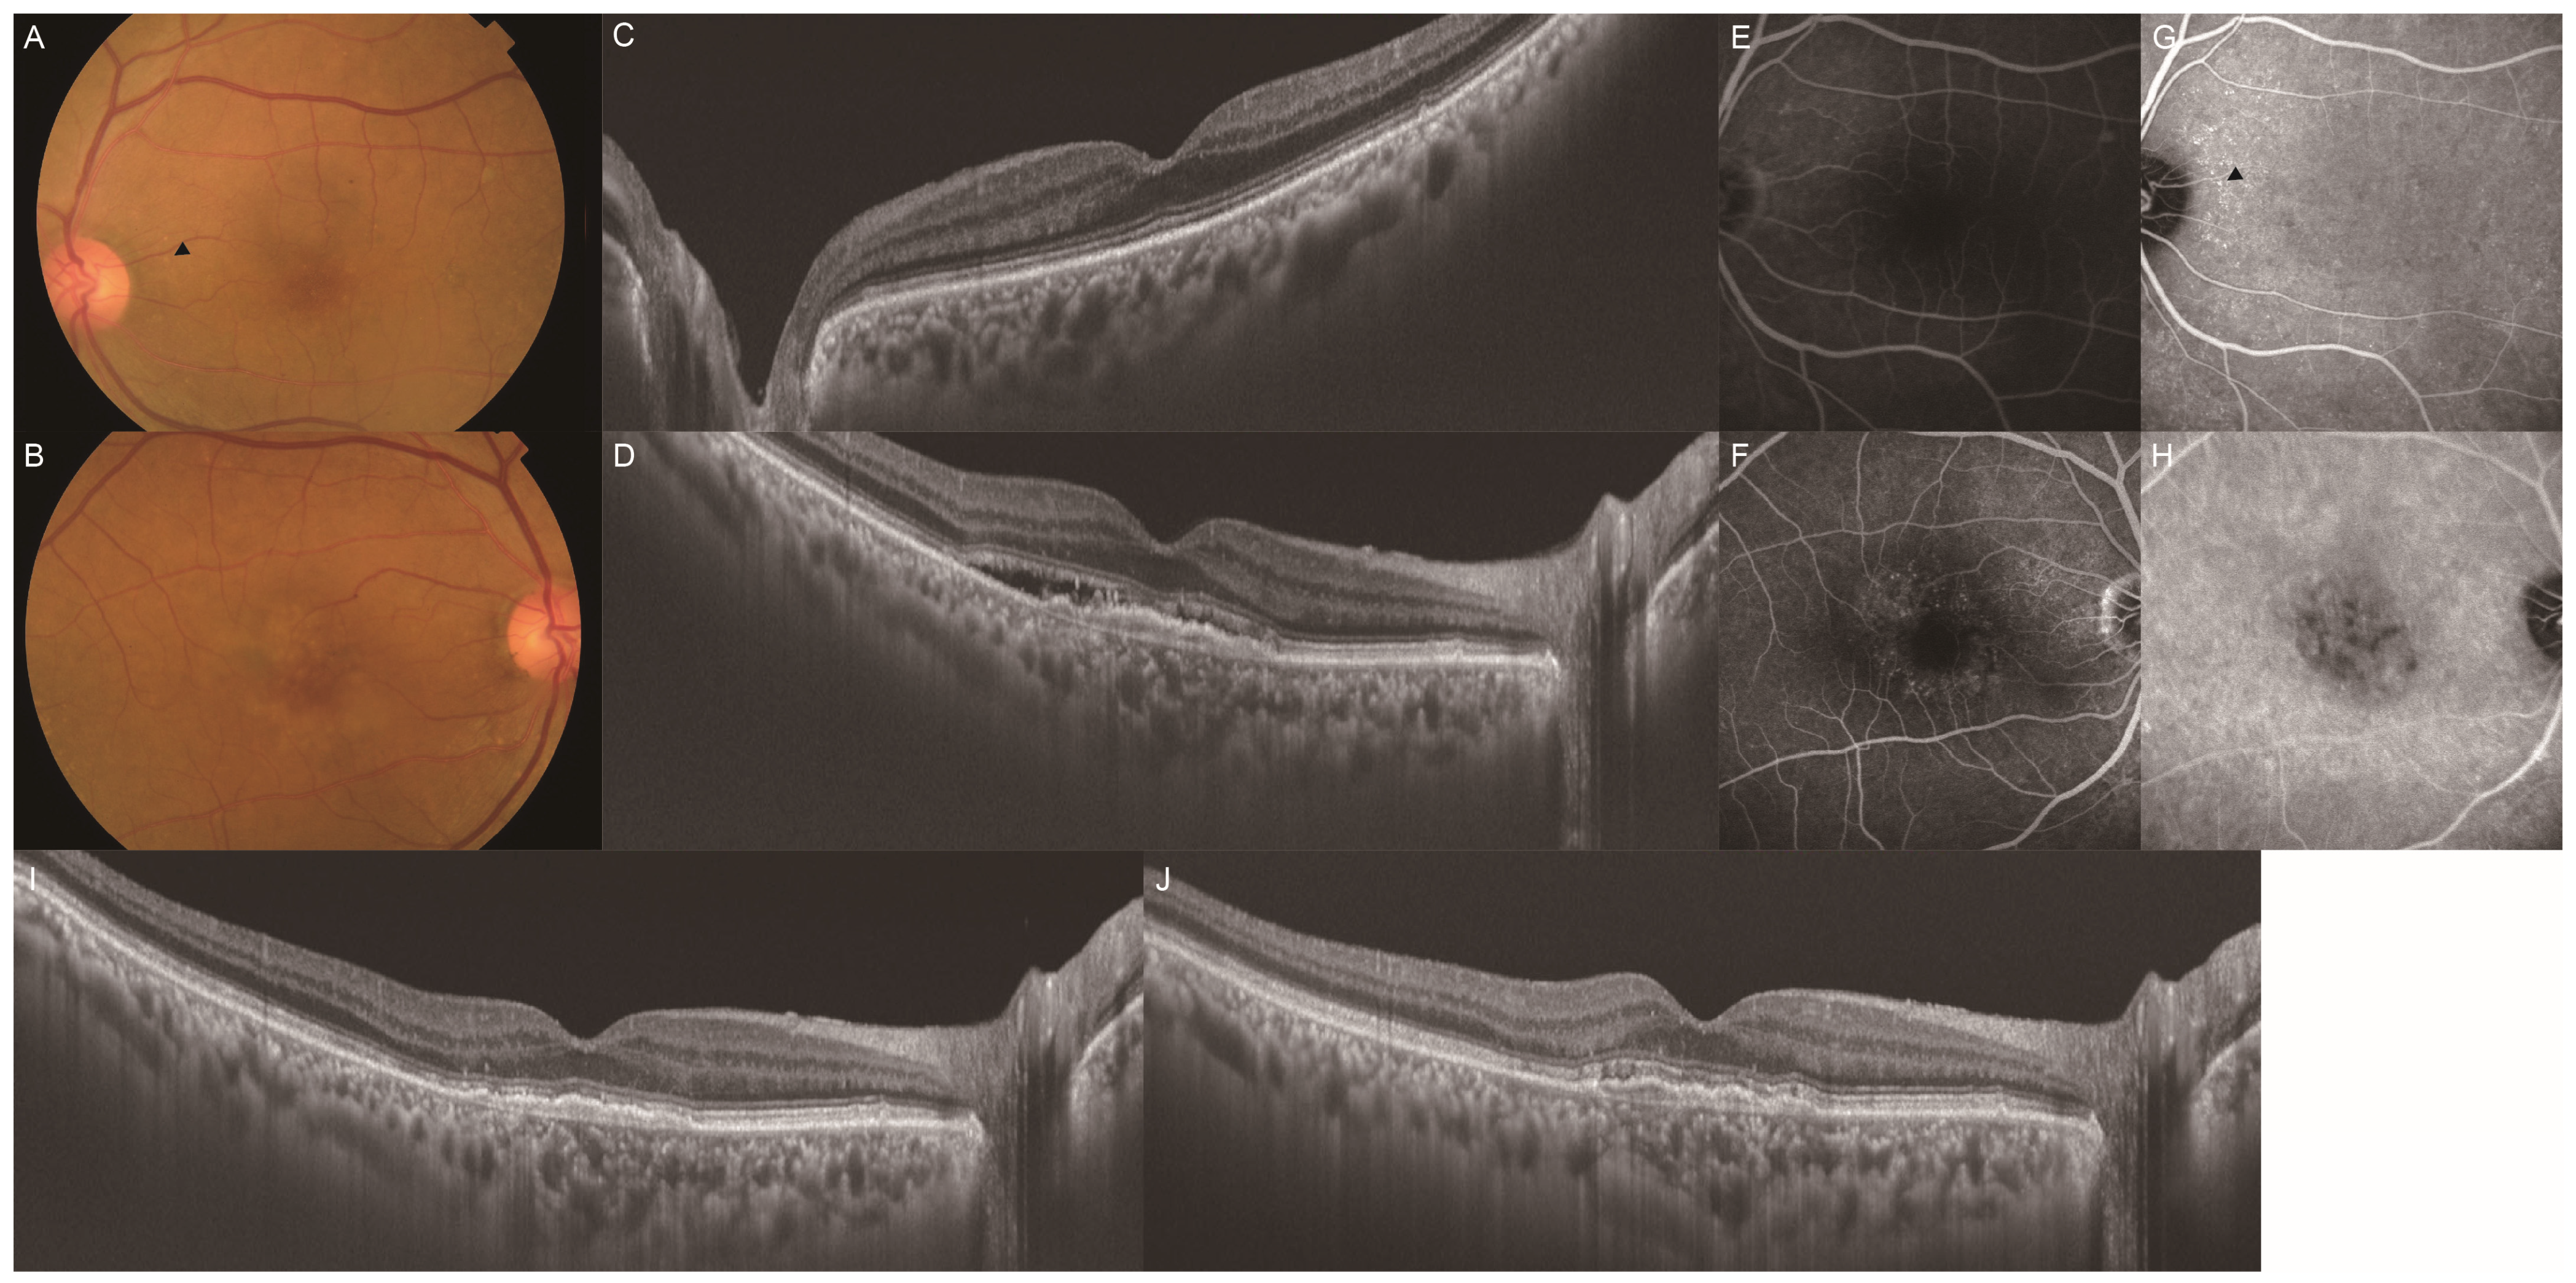

Clinical Characteristics of Punctate Hyperfluorescence Spots in the Fellow Eye of Patients with Unilateral Macular Neovascularization with No Drusen

- Tsujikawa, A.; Ojima, Y.; Yamashiro, K.; Ooto, S.; Tamura, H.; Nakagawa, S.; Yoshimura, N. Punctate hyperfluorescent spots associated with central serous chorioretinopathy as seen on indocyanine green angiography. Retina 2010, 30, 801–809. [Google Scholar] [CrossRef] [PubMed]

- Park, S.J.; Kim, B.H.; Park, K.H.; Woo, S.J. Punctate hyperfluorescence spot as a common choroidopathy of central serous chorioretinopathy and polypoidal choroidal vasculopathy. Am. J. Ophthalmol. 2014, 158, 1155–1163. [Google Scholar] [CrossRef] [PubMed]

- Kim, H.; Lee, J.H.; Kwon, K.Y.; Byeon, S.H.; Lee, S.C.; Lee, C.S. Punctate hyperfluorescent spots associated with polypoidal choroidal vasculopathy on indocyanine green angiography. Ophthalmic. Surg. Lasers Imaging Retina. 2015, 46, 423–427. [Google Scholar] [CrossRef]

- Kang, H.G.; Han, J.Y.; Kim, M.; Byeon, S.H.; Kim, S.S.; Koh, H.J.; Lee, C.S. Pachydrusen, choroidal vascular hyperpermeability, and punctate hyperfluorescent spots. Graefes Arch. Clin. Exp. Ophthalmol. 2021, 259, 2391–2400. [Google Scholar] [CrossRef]